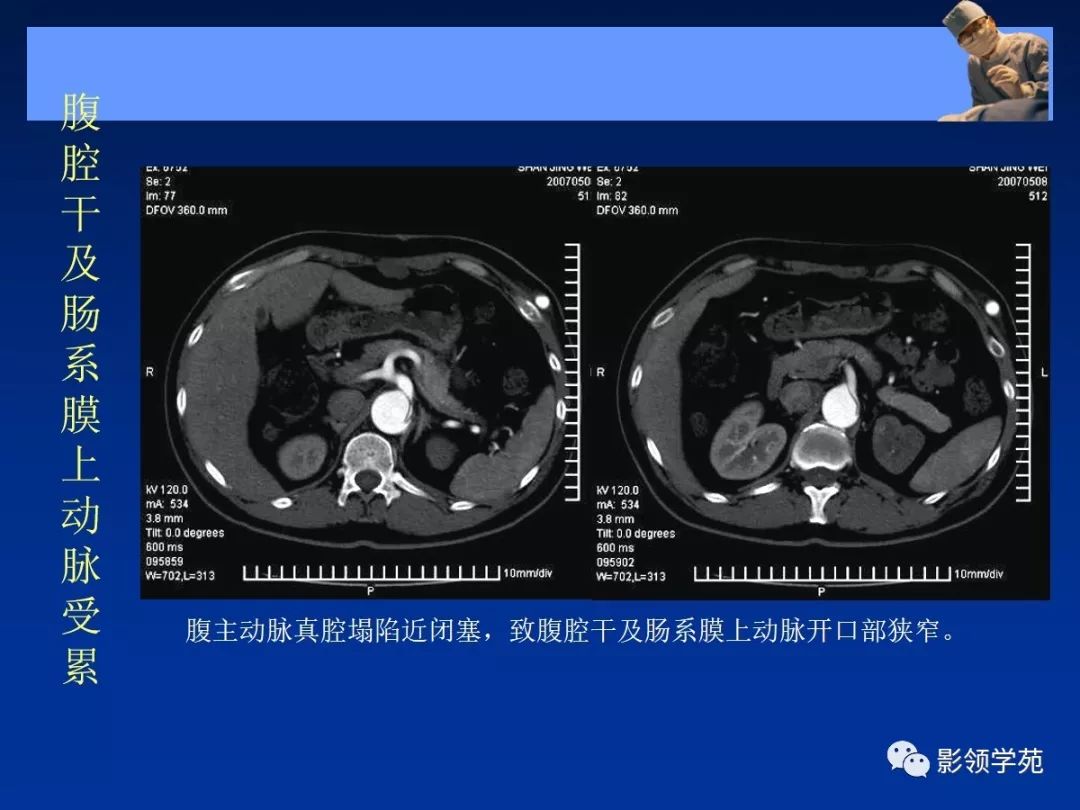

典型AD:

病理学特点:

- 内膜撕裂

- 真假“双腔” ,存在交通

- 远段同时存在再破口